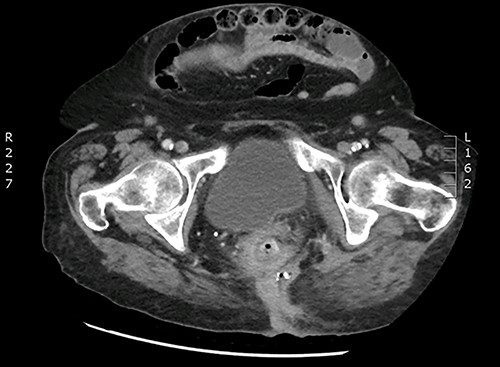

A 90-year-old woman presented with abdominal pain and pneumaturia; in her medical history we find a laparotomy mesh rectopexy 15 years ago. CT scan showed inflammation around the mesh that can also be seen entering the bladder (Figs 5 and 6).